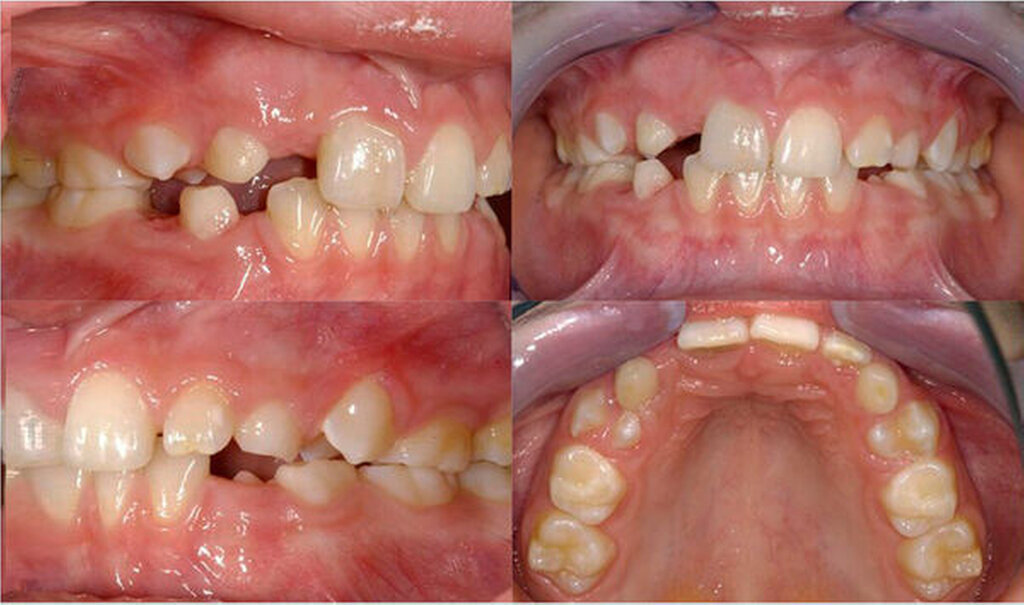

Während die ersten beiden Therapievarianten in der Fortbildung „Die Einzelzahnlücke“ ausführlich dargestellt wurden, sollen im Folgenden an zwei Autotransplantationsfällen die Indikationsbreite, das methodische Vorgehen und die Vorteile und Risiken gegenüber den Alternativen dargestellt werden.

In beiden Falldarstellungen wurden diese Bedingungen eingehalten. Eine Besonderheit stellt die Kombination von kieferorthopädischem Lückenschluss und Autotransplantation im zweiten Fall dar. Hier war vor der Rekonstruktion mittels Kompositaufbau eine Bewegung des Transplantats und der rechten Seitenzahnreihe erforderlich. Beides gestaltete sich ohne Probleme und sollte auch beim Verlust mehrerer Schneidezähne bedacht werden. Der Lückenschluss im Unterkiefer nach Keimentnahme konnte mithilfe skelettaler Verankerung ebenfalls reibungslos erfolgen. Es sollte jedoch wie beim kieferorthopädischen Lückenschluss die Anlage der dritten Molaren in der verkürzten Zahnreihe geprüft werden, um für den zweiten Molaren des Gegenkiefers einen Antagonisten zu haben. Ziel des Beitrags war es, die Autotransplantation nach Frontzahnverlust und Aplasie ins differenzialdiagnostische und -therapeutische Spektrum als gleichberechtigte Variante einzubeziehen.